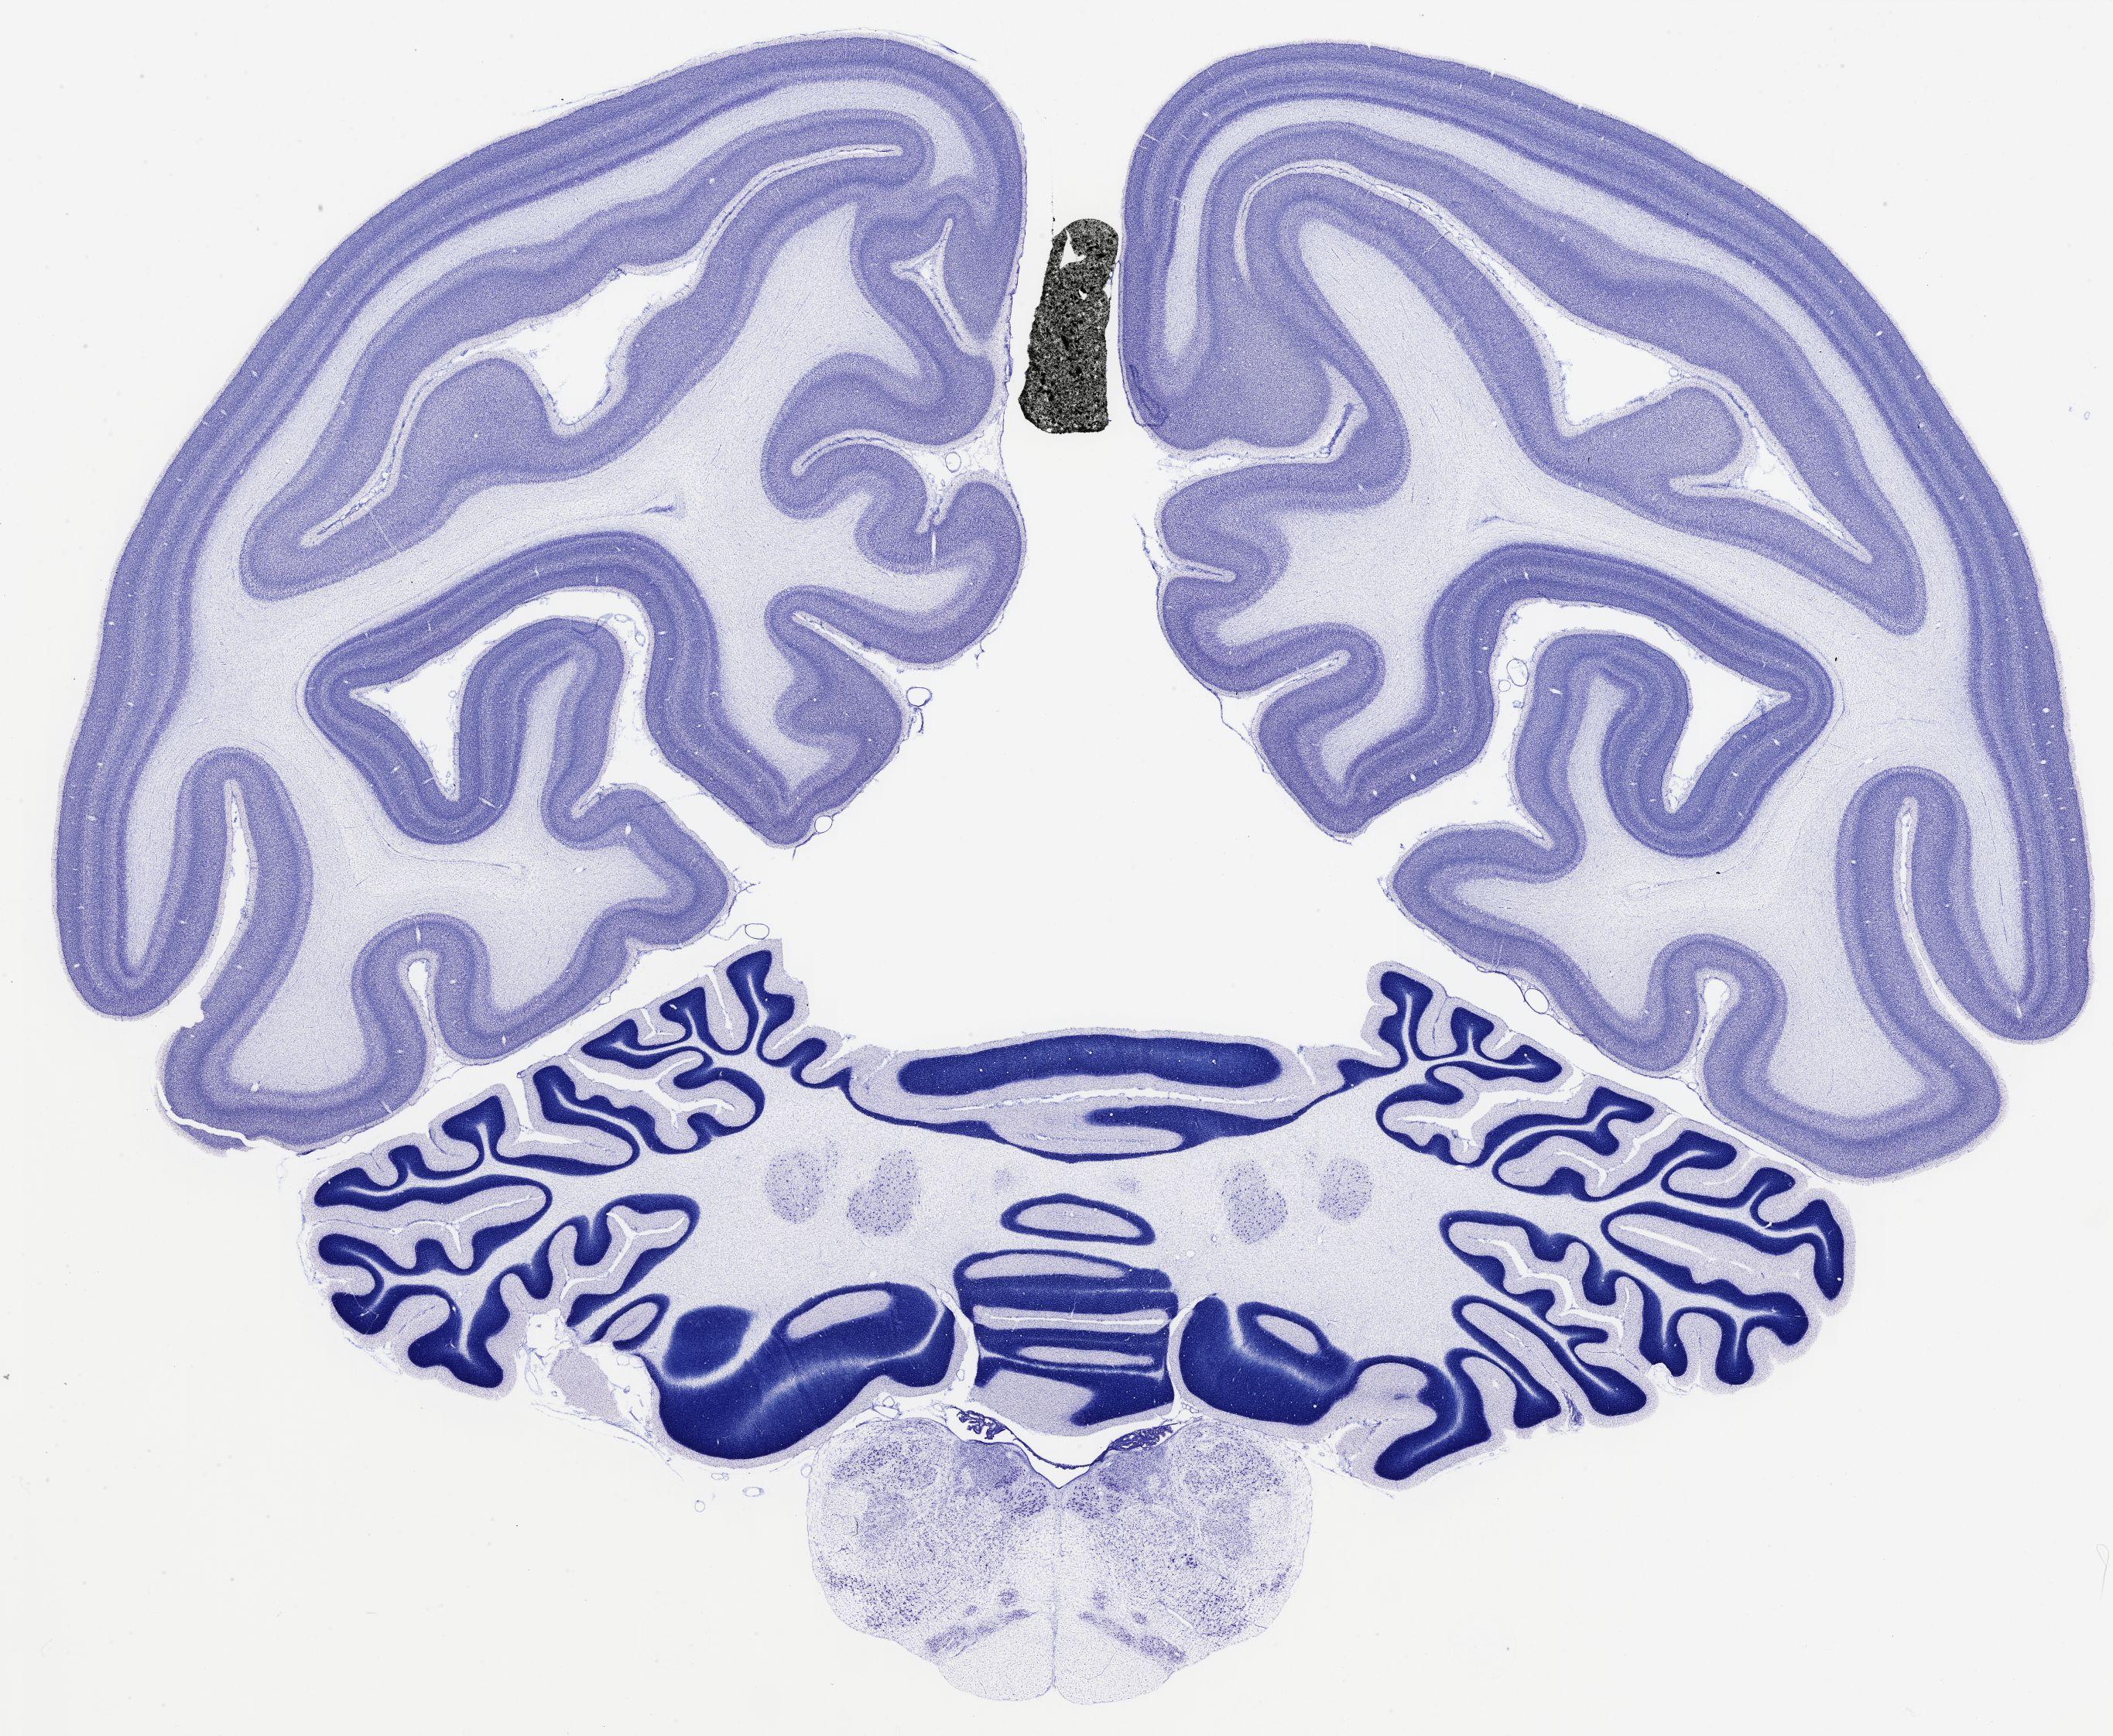

Datasets -> Chlorocebus Aethiops -> Nissl, coronal, histo, Whole-Brain, adult

[ Metadata ]   ·   Source: NeuroScience Associates

Displaying Sections 561 thru 600 of 740 Sections for this Dataset